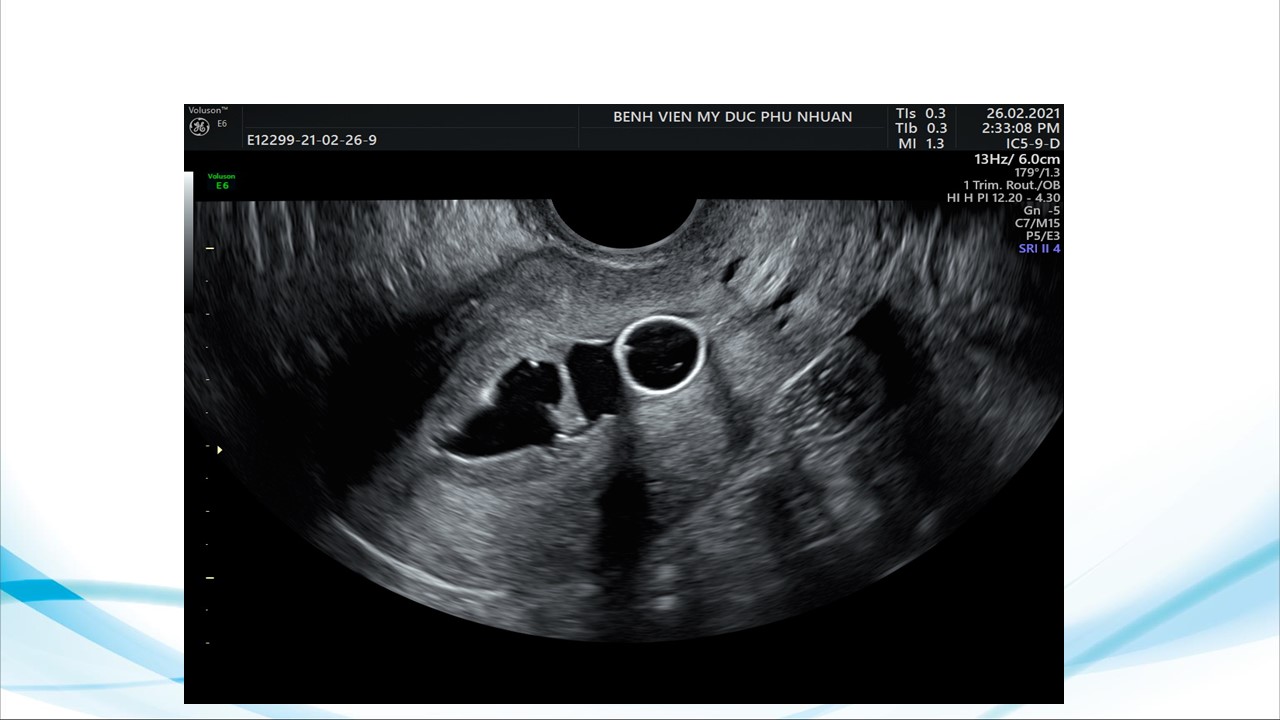

Siêu âm sử dụng chật tương phản trong phụ khoa

BS. CKI Phạm Thị Phương Anh - Bệnh viện Mỹ Đức